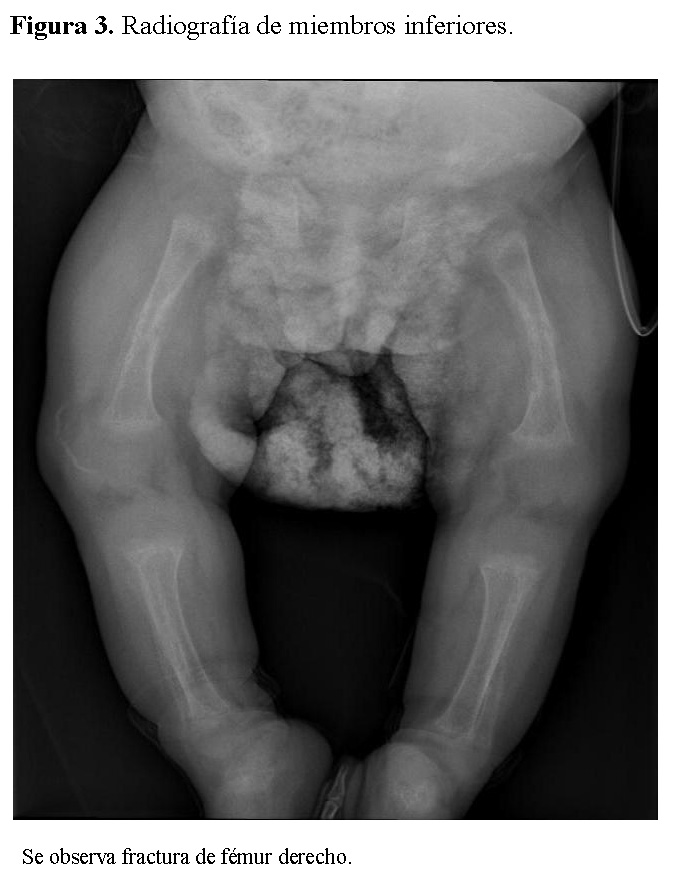

La radiografía de tórax mostró infiltrados parenquimatosos heterogéneos bilaterales, engrosamiento pleural y fracturas costales derechas en fase de consolidación (Figura 1). Las radiografías de huesos largos evidenciaron osteopenia severa, reacción perióstica y múltiples fracturas patológicas, incluyendo húmero derecho e izquierdo, cúbito derecho y fémur derecho (Figuras 2 y 3).

Figura 3.